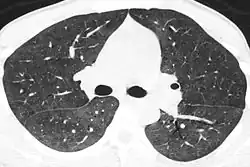

Диагноз устанавливается на основании данных рентгенографии и, предпочтительно, компьютерной томографии, демонстрирующей картину диффузных или диффузно-мозаичных зон снижения воздушности лёгочной ткани по типу «матового стекла». На этом фоне оксигенация артериальной крови значительно ниже ожидаемой при наблюдающейся клинической картине. Диагноз подтверждается обнаружением предполагаемого патогена в мокроте или при исследовании бронхоальвеолярного смыва. При микроскопии окрашенного материала обнаруживаются характерные кисты[5], имеющие вид «раздавленных шариков для пинг-понга». При микроскопии биоптата лёгкого выявляется утолщение альвеолярных перегородок с «пушистым» эозинофильным экссудатом в просвете альвеол.